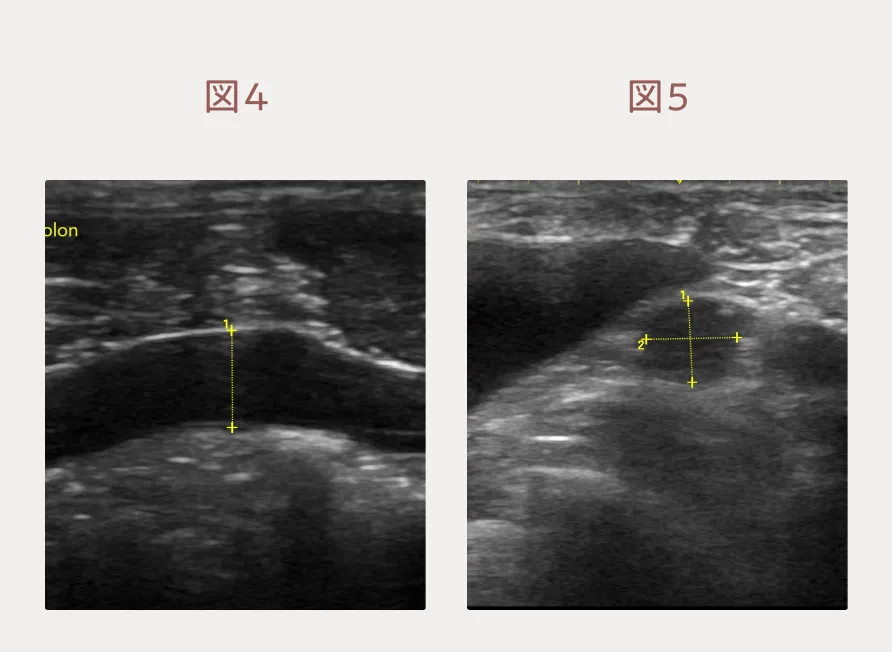

ご家族は抗がん剤治療を希望されましたので、週1回の抗がん剤治療を開始しました。抗がん剤の投与当日には病変が増悪しており、エコー検査で大腸の一部は大腸壁の肥厚・層構造の消失・結腸リンパ節腫大を認めました。(図4、5)この患者さんのリンパ腫は細胞形態的には悪性度としては中間ですが、高悪性度寄りのリンパ腫である可能性があります。